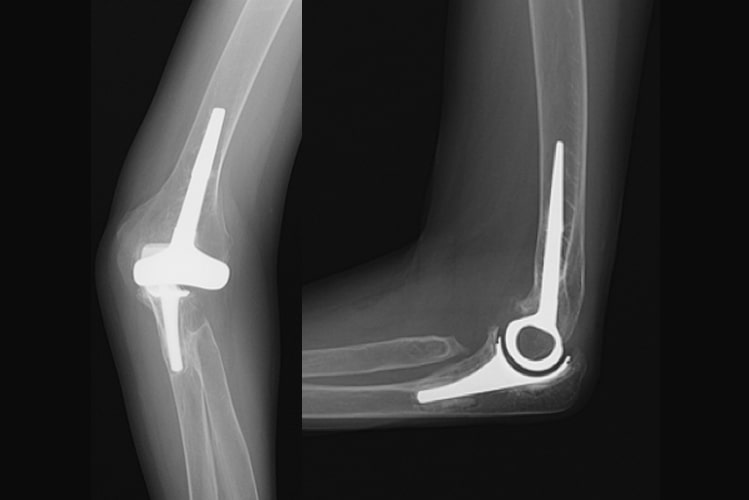

表面置換型人工肘関節写真

表面置換型人工肘関節

半拘束型人工肘関節写真

半拘束型人工肘関節

人工手関節写真

人工手関節

原因

関節リウマチにより手や指、肘の関節が破壊されて変形や疼痛が生じます。滑膜炎により指の腱が切れてしまうこともあります。関節リウマチの治療の基本は内服加療ですが、骨破壊が生じてしまったり、腱が断裂した場合は手術が必要です。

治療方針

腱が切れた場合は腱移行や腱移植を行って治療します。手の腫れや痛みが持続した場合、関節破壊の程度に合わせて滑膜切除、関節形成、関節固定を追加します。最近は人工手関節置換術を行う場合もあります。指や肘の関節リウマチについても、腫れや痛みが持続する場合は人工関節置換術を行うことで生活レベルの向上が期待できます。